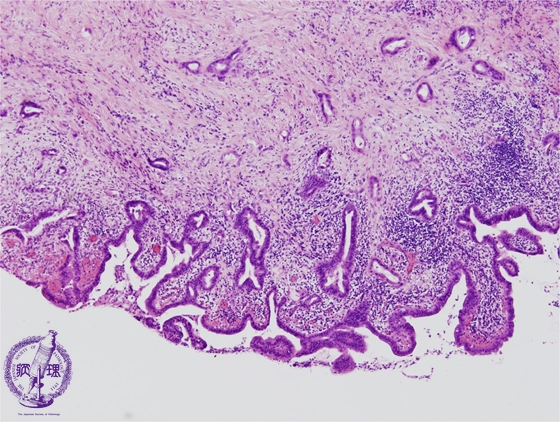

Microscopic image (HE stain, mid-power view): Cancer infiltrates diffusely throuought the mucosa and into the wall.